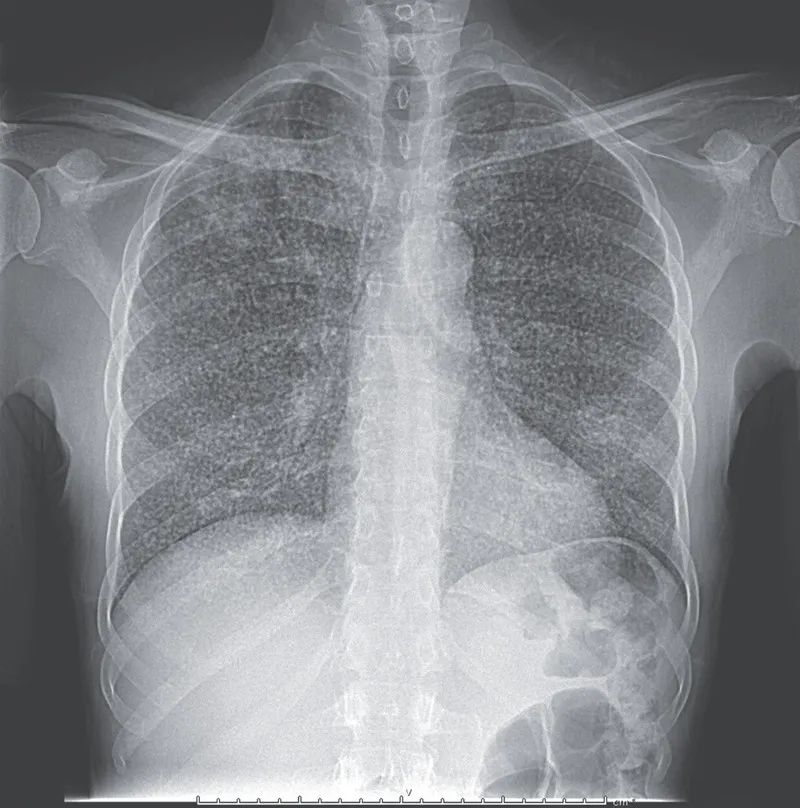

X胸胸片显示广泛分布的均匀大小的结节遍布两个肺野,提示粟粒性肺结核。